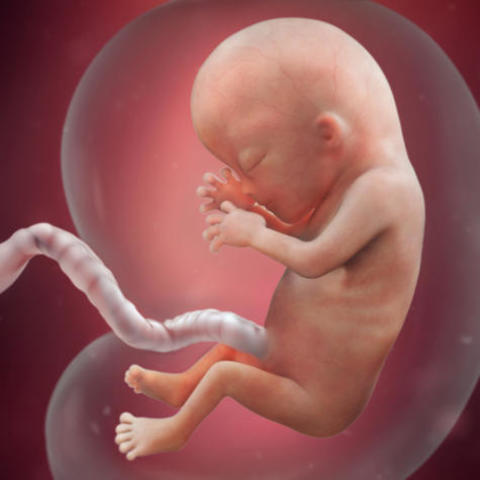

• Week Eight: First Prenatal Visit

Week Eight: First Prenatal Visit

The heart is beating around 150 beats per minute as the face begins to take shape. Limbs are still growing while eyes are developing.

• Week Nine

Week Nine

The cartilage for bones is begining to califiy; arms and legs can begin to flex, but you cannot feel it, so dont lie. The heart and brain are now starting to fully develop.